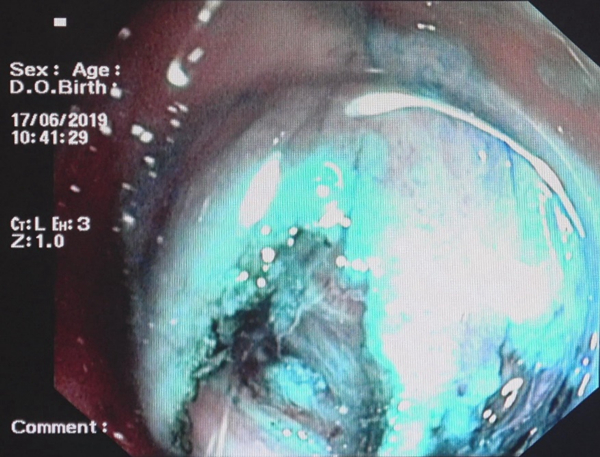

术后肠道内创面展示